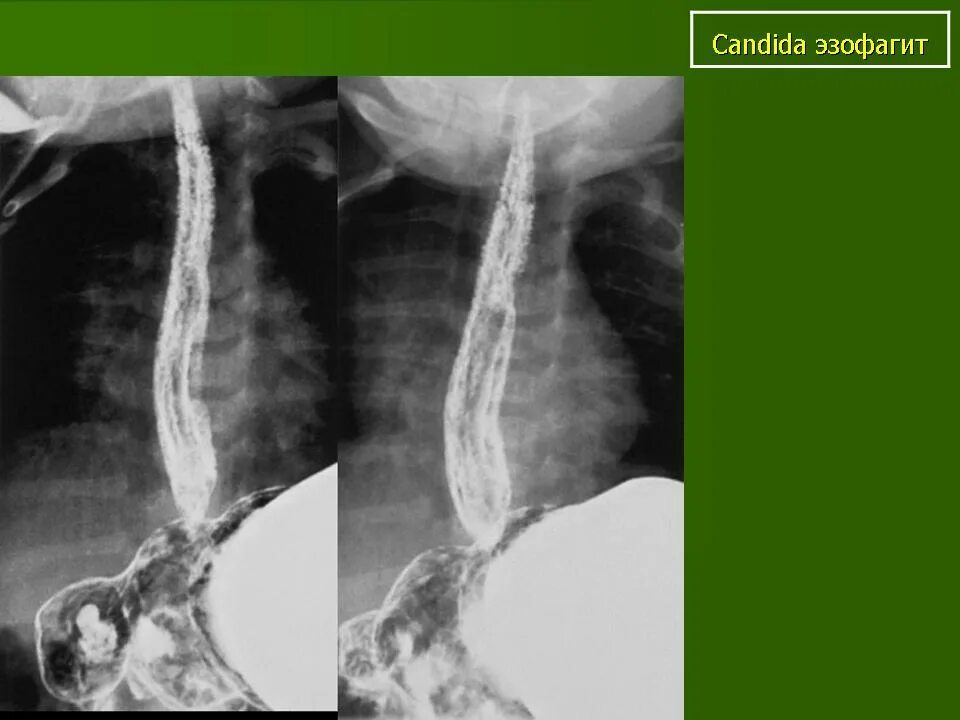

Раздражение пищевода